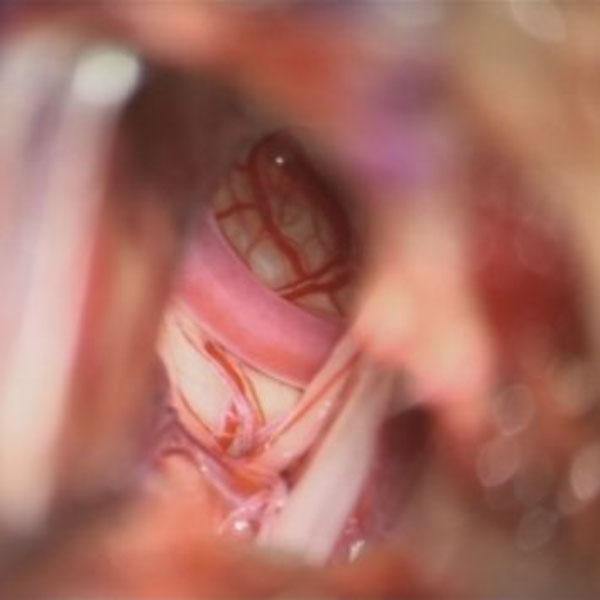

手術中

処置前

処置後